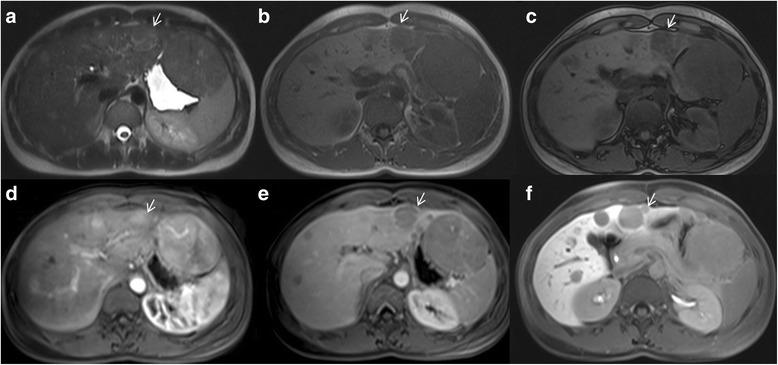

Liver Imaging Reporting and Data System (LI-RADS) is a system for interpreting and reporting of imaging features on multidetector computed tomography (MDCT) and magnetic resonance (MR) studies in patients at risk for hepatocellular carcinoma (HCC). American College of Radiology (ACR) sustained the spread of LI-RADS to homogenizing the interpreting and reporting data of HCC patients. Diagnosis of HCC is due to the presence of major imaging features. Major features are imaging data used to categorize LI-RADS-3, LI-RADS-4, and LI-RADS-5 and include arterial-phase hyperenhancement, tumor diameter, washout appearance, capsule appearance and threshold growth. Ancillary are features that can be used to modify the LI-RADS classification. Ancillary features supporting malignancy (diffusion restriction, moderate T2 hyperintensity, T1 hypointensity on hapatospecifc phase) can be used to upgrade category by one or more categories, but not beyond LI-RADS-4. Our purpose is reporting an overview and update of major and ancillary MR imaging features in assessment of HCC.

肝脏影像报告和数据系统(LI-RADS)是一种用于解读和报告肝细胞癌(HCC)高危患者多排螺旋计算机断层扫描(MDCT)和磁共振成像(MR)检查影像特征的系统。美国放射学会(ACR)推动了LI-RADS的推广,以统一HCC患者的解读和报告数据。HCC的诊断基于主要影像特征的存在。主要特征是用于对LI-RADS-3、LI-RADS-4和LI-RADS-5进行分类的影像数据,包括动脉期强化、肿瘤直径、廓清表现、包膜表现和阈值生长。辅助特征可用于修改LI-RADS分类。支持恶性的辅助特征(扩散受限、T2中等度高信号、肝胆期T1低信号)可用于将类别提升一级或多级,但不超过LI-RADS-4。我们的目的是报告在HCC评估中主要和辅助MR成像特征的概述及更新情况。